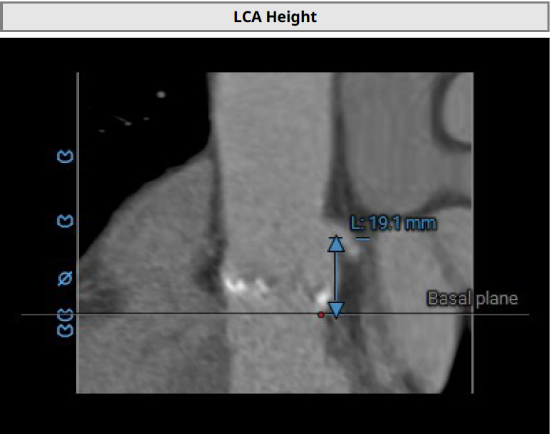

主动脉瓣瓣环及其他基本平面测量

主动脉瓣瓣上及瓣下多平面测量